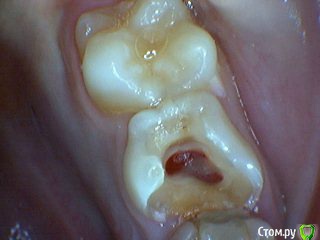

Давлетшин Опубликовано 29 декабря, 2017 Поделиться Опубликовано 29 декабря, 2017 (изменено) Друзья. Расскажите, не поменялось ли ваше отношение к пульпотеку и пр.Почему пломбы поверх пульпотеку такие ужасно жёлтые? Что сделать можно. Или что я делаю не так? "Друзья" так приятно перед новым годом. К пульпотеку не поменялось (устраивает вполне) , к пульподенту скептическое отношение, хоть и тоже работаю. Пломбы сразу желтые или через полгода - год- два? Очень тяжело что то советовать он лайн не видя как человек работает. В фото первая цифра пациент, вторая-третья номер зуба, четвертая порядок фото. Я после наложения пульпотека , стараюсь убрать излишки, или аккуратно на устья каналов накладываю, в пульповую камеру СИЦ, и сверху пломбу, Убрать излишки и со стенок, аккуратно в том числе и бором. В третьем клиническом случае, неудача. Зуб удалил сам же через 3 месяца. причину вижу в том что на рентгене не увидел (или так сделали снимок?) вертикальный тип рассасывания практически до бифуркации., может и потому что ребенок ОЧЕНЬ плохо сидел. За фото не пинайте сильно, не инстаграмм все таки,да и тяжело ребенка лечить и фотки делать. или наоборот пинайте может лучше начнем фоткать. P.s. Добавлю протокол как лечу с пульпотеком, хр.фибр.пульпит1. анестезия2. кофер ( если дает)3. раскрытие кариозной и пульповой камеры4. удаление коронковой пульпы маленьким эскаватором, я стараюсь "отрубать" пульпу5. остановка кровотечения сухим ватным шариком, 0,5-1-2 минуты6. пульпотек на устья7 СИЦ в пульповую камеру8 со стенок остатки пульпотека соскребаю бором фиссурным , цилиндрическим, там же фальц9. Пломба. может что то и зыбыл ну и оценка только позитивная перед НГ Изменено 29 декабря, 2017 пользователем Давлетшин 2 Ссылка на комментарий